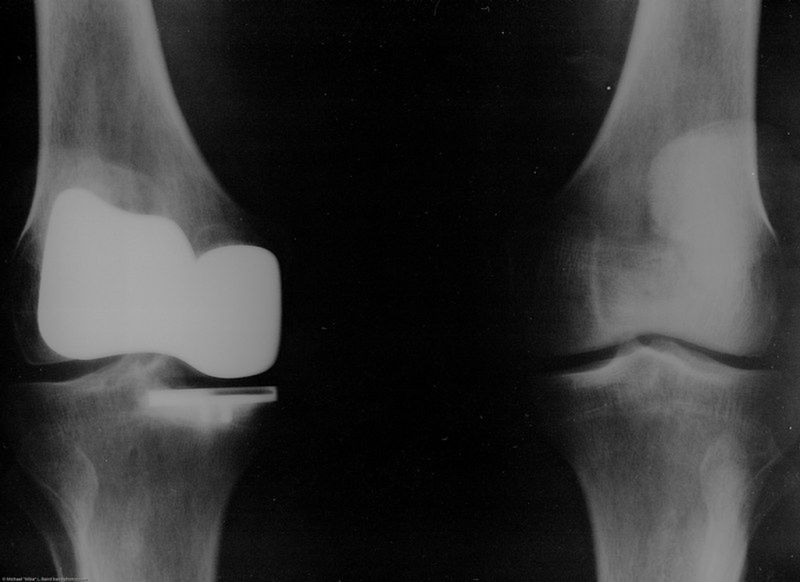

/ 12Reumatoidalne zapalenie stawów - RTG

Obraz

© mikebaird, lic. CC BY 2.0

/ 12Reumatoidalne zapalenie stawów - diagnostyka

Jak się diagnozuje RZS?

Pierwszy krok w diagnostyce RZS to wizyta u reumatologa, który zbierze dokładny wywiad, zbada stawy pod kątem stanu zapalnego, deformacji i guzków reumatoidalnych itp. Wykonuje się także badania krwi i zdjęcie rentgenowskie. Diagnoza będzie postawiona na podstawie określonego wzorca symptomów, obszaru i rozmiaru stanu zapalnego, badania krwi i RTG. Pełne rozpoznanie może wymagać kilku wizyt.